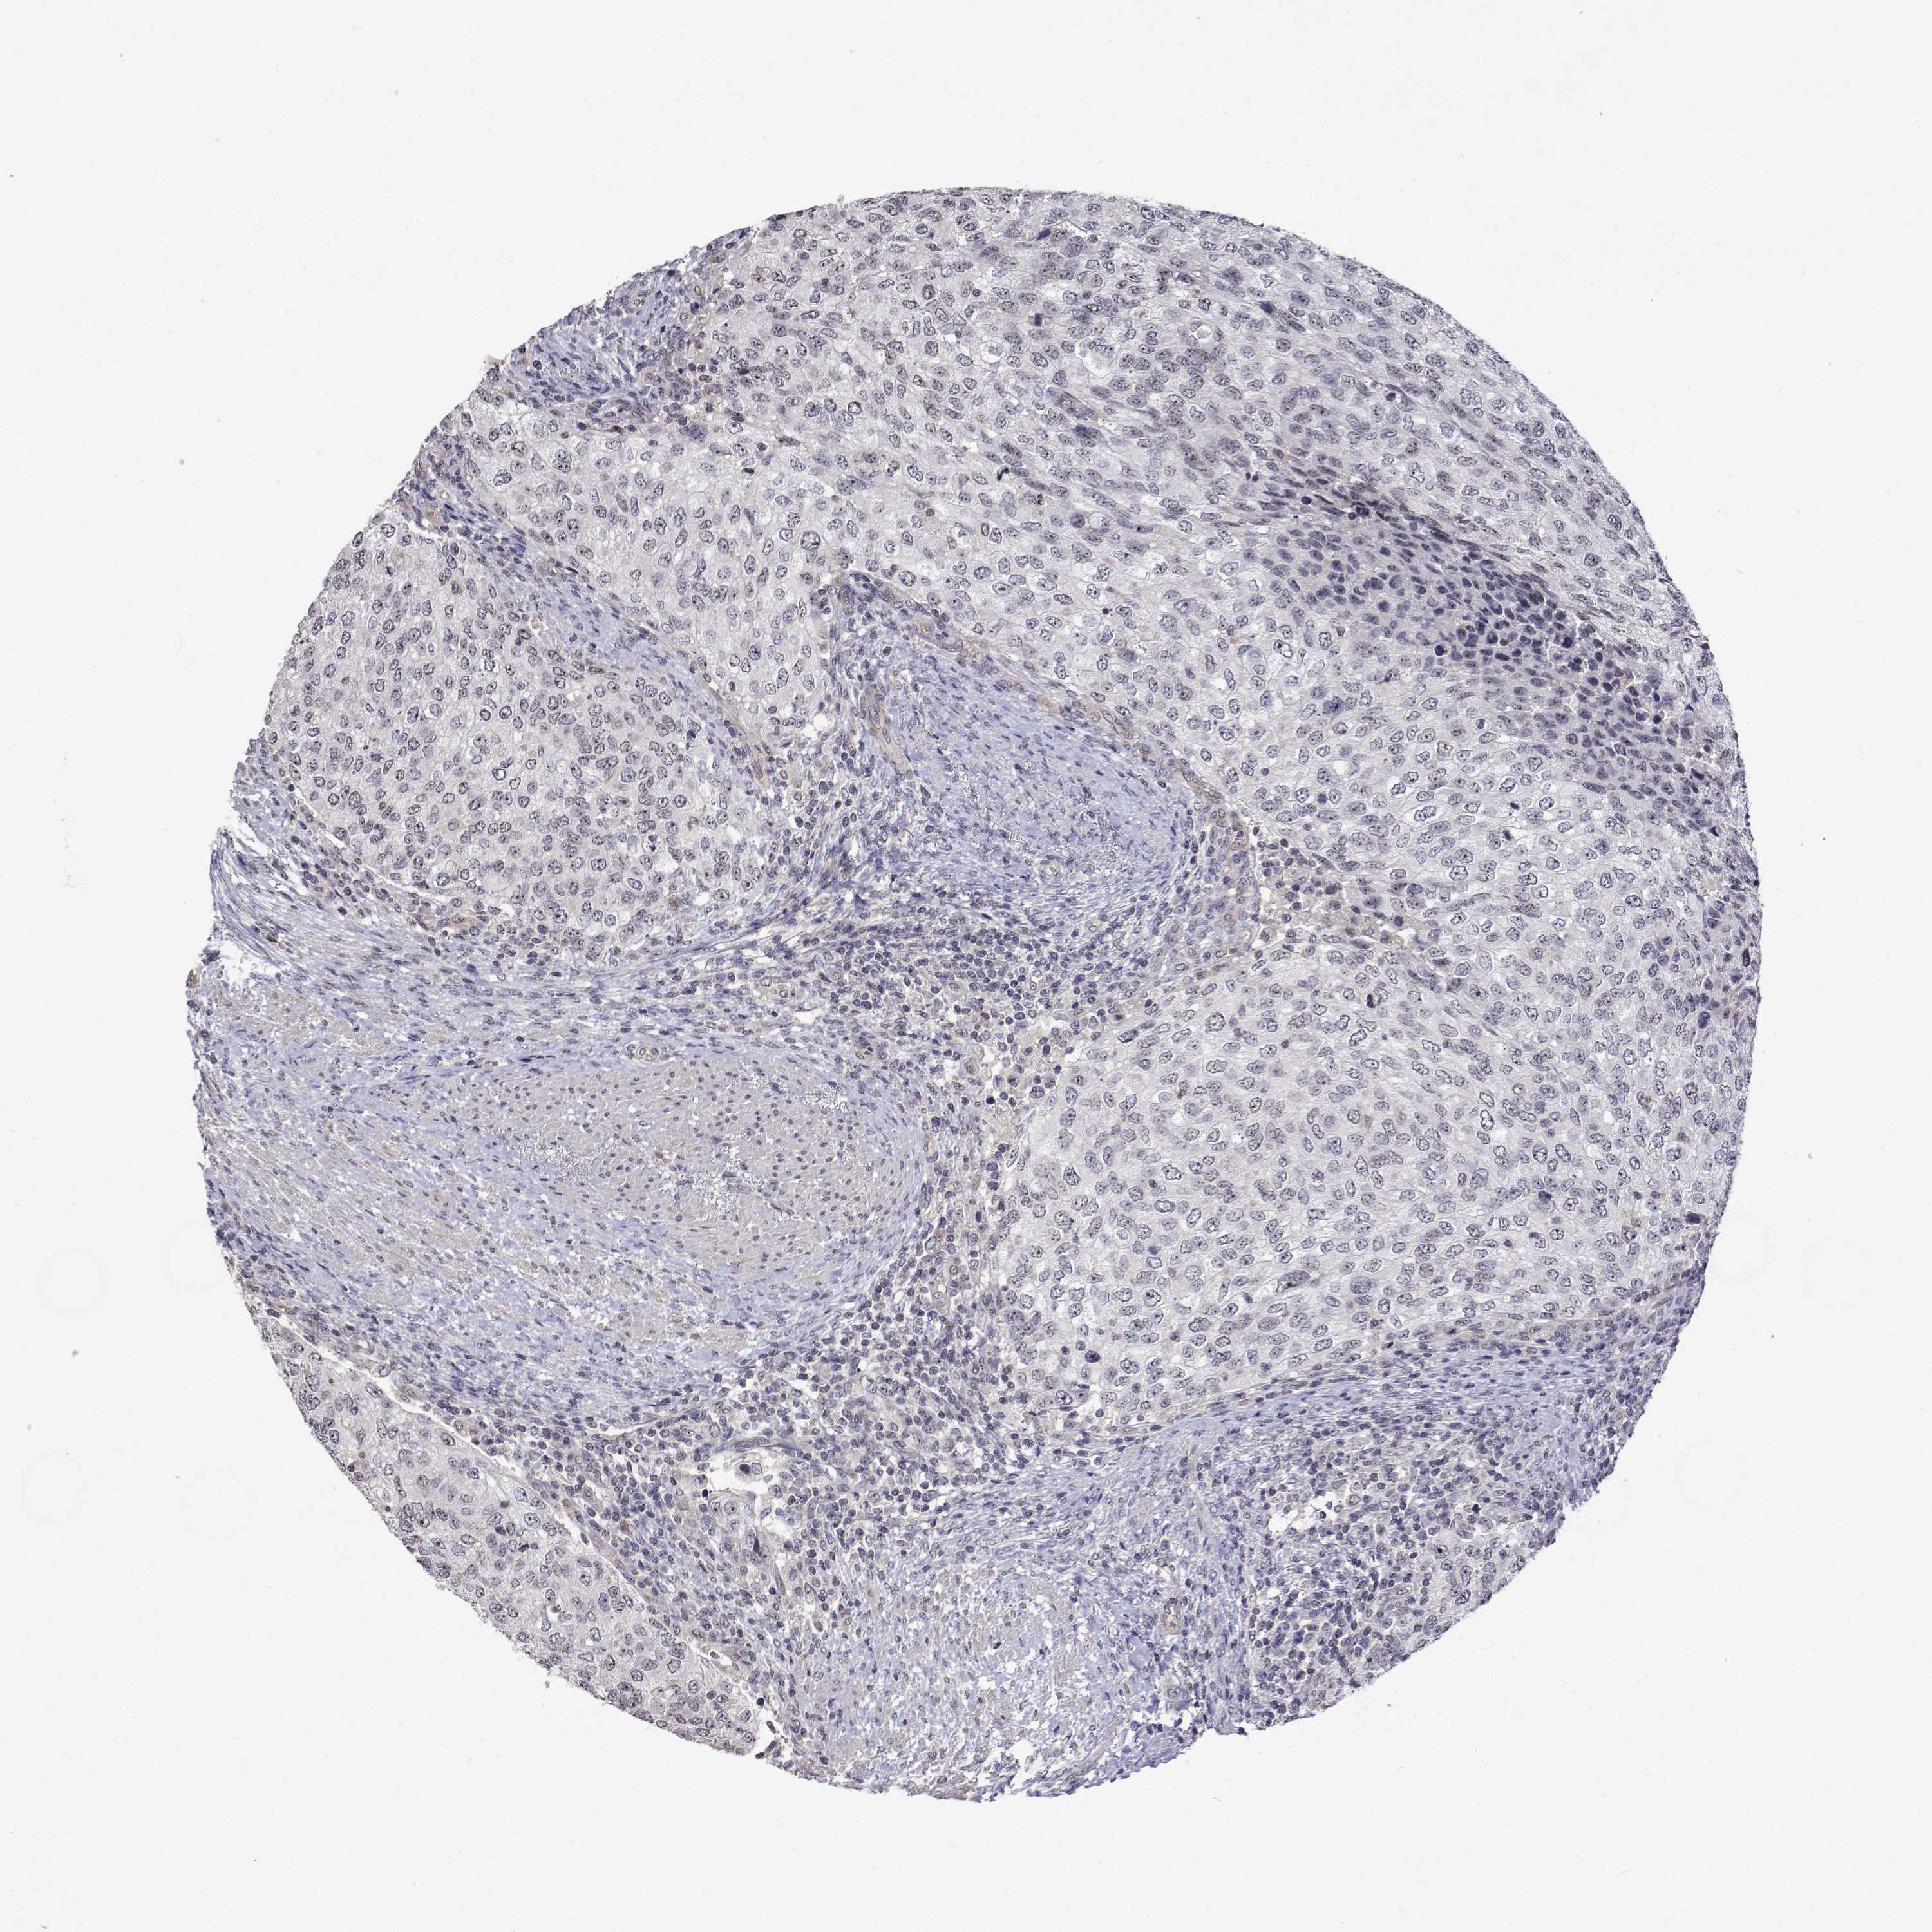

UROTHELIAL CANCER - Protein expressioni

A mouse-over function shows sample information and annotation data. Click on an image to view it in a full screen mode. Samples can be filtered based on level of antibody staining by selecting one or several of the following categories: high, medium, low and not detected. The assay and annotation is described here.

Antibody stainingi

Antibody staining in the annotated cell types in the current human tissue is reported as not detected, low, medium, or high, based on conventional immunohistochemistry profiling in selected tissues. This score is based on the combination of the staining intensity and fraction of stained cells.

Each image is clickable and will lead to virtual microscopy that enables deeper exploration of all samples and also displays staining intensity scores, fraction scores and subcellular localization as well as patient and tissue information for each sample.

Antibody HPA044171

Antibody HPA050400

Urothelial carcinoma, High grade

Urothelial carcinoma, NOS

Urothelial carcinoma, Low grade